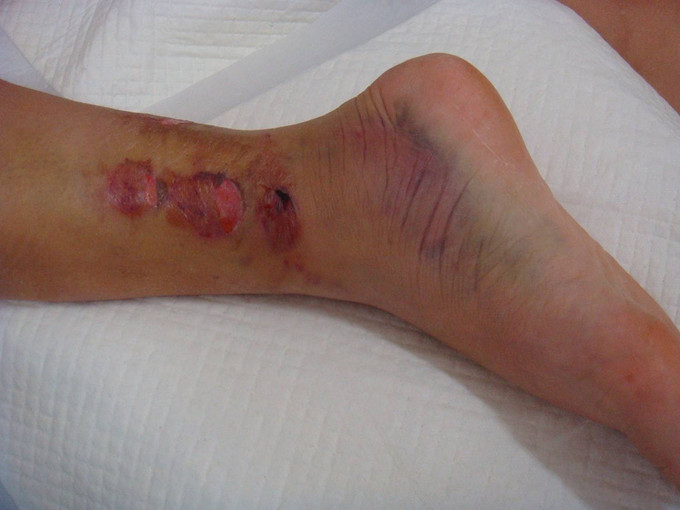

右踝关节肿胀明显,皮下瘀斑。右踝关节局部压痛明显。右足趾屈背伸因为疼痛活动较弱。右足背动脉搏动良好,末梢血运良好。

诊断:右胫腓骨远端粉碎性骨折 患者为右plion骨折,入院后局部肿胀明显,给予患肢抬高,冷敷,消肿等对症治疗,密切观察患肢皮肤情况,带皮肤条件良好的情况下,约2周后行右三踝骨折切开复位钢板内固定术。